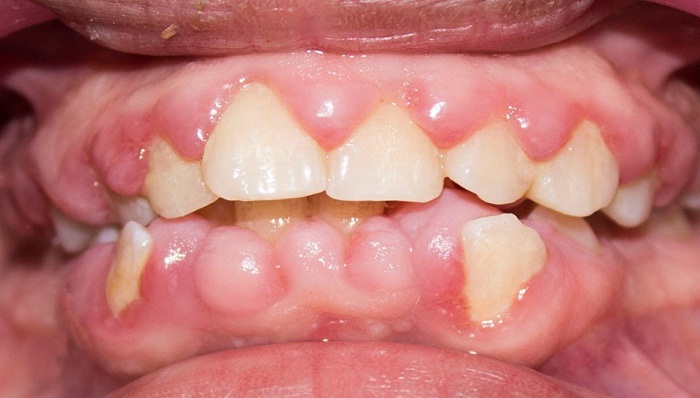

Entre los antecedentes odontológicos se reportaron cuatro gingivectomías entre 2004 y 2008. En el examen clínico extraoral la paciente evidenciaba quintos asimétricos, tercio medio disminuido, perfil convexo e incompetencia labial. En el examen clínico intraoral se registró sobremordida horizontal y vertical, malposiciones y apiñamiento dental. Periodontalmente, se observó aumento en el volumen del tejido gingival en las superficies vestibulares, palatinas y linguales de incisivos, caninos y premolares. El sondaje reveló bolsas gingivales con un rango de profundidad de 4 a 6 mm, acompañado de eritema, sangrado y cálculos subgingivales. La paciente tenía una higiene oral deficiente con un porcentaje de placa del 84,3 %, según el Índice de O’Leary (figura 1). Se notificó que su frecuencia de cepillado era de una vez al día y que no utilizaba elementos complementarios de higiene oral. La figura 2 corresponde a la radiografía panorámica en la que se observan crestas óseas de altura normal.

El diagnóstico periodontal fue agrandamiento gingival inducido por medicamentos. Se dio un pronóstico reservado, debido a los antecedentes sistémicos, los hábitos de higiene oral, el índice de placa y los mantenimientos periodontales poco constantes en el tiempo. La paciente y su acudiente aceptaron y firmaron el consentimiento informado.